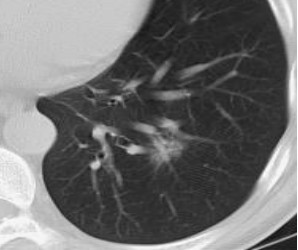

磨玻璃结节又叫磨玻璃影、毛玻璃结节等,在CT影像上跟磨砂玻璃一样故命名。

上次我们提到了磨玻璃密度影,它在CT上的表现是由于肺实质密度轻度增高,其中支气管血管束未被掩盖,可为斑片状或结节状,其中就包括磨玻璃结节,磨玻璃密度影可大可小,小于3公分磨玻璃密度影叫磨玻璃结节。

肺部结节分为三种:实性结节、磨玻璃结节、混合实性结节。磨玻璃结节是肺部结节中的一种特殊类型,指肺内局灶性、结节状、淡薄密度增高影,结节内部原有结构如血管、气道及小叶间隔仍可见。

磨玻璃结节可分为两大类:1.不含实性成分的为单纯性磨玻璃结节; 2.伴有实性成分、掩盖部分肺纹理的为混合性磨玻璃结节。